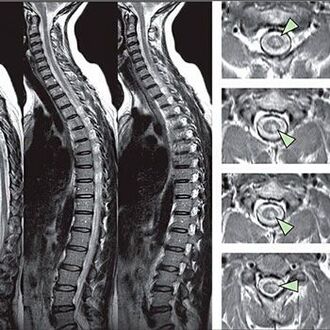

Um Anzeichen von Sensitivitätsstörungen zu identifizieren, werden spezielle Funktionstests durchgeführt. Die informativste Option für die Diagnose von instrumentellen Methoden ist die Leistung von X -Strahlen. Für eine umfassende Untersuchung der Wirbelsäule werden jedoch häufig Magnetresonanz und TC durchgeführt. Im Falle eines Verdachts auf kardiovaskuläre Systemkrankheiten wird der Patient empfohlen, sich dem EKG -Verfahren zu unterwerfen.